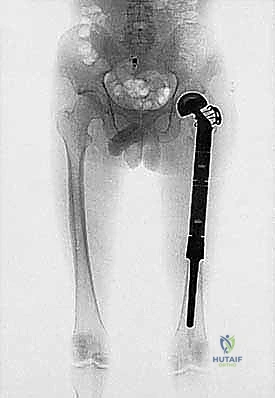

- التصوير الشعاعي العادي (X-rays): الخطوة الأولى للكشف عن أي تدمير عظمي أو تكوّن عظمي غير طبيعي.

- التصوير بالرنين المغناطيسي (MRI): الأداة الذهبية لتحديد حجم الورم بدقة، مدى انتشاره في النخاع العظمي، وعلاقته بالأنسجة الرخوة والأوعية الدموية والأعصاب.

- التصوير المقطعي المحوسب (CT Scan): لتقييم القشرة العظمية والبحث عن نقائل في الرئتين.

2. إعادة بناء وتثبيت العظم والمفاصل المصابة (Reconstruction)

بمجرد إزالة الورم والفراغ العظمي الكبير، يبدأ بناء الطرف الجديد. هنا يأتي دور أنظمة الأطراف الاصطناعية الداخلية.

* يتم تحضير القنوات النخاعية للعظام المتبقية.

* يتم إدخال سيقان الغرسة (إما باستخدام الأسمنت العظمي الطبي للتثبيت الفوري، أو سيقان غير أسمنتية مغطاة بمواد مسامية تسمح للعظم الطبيعي بالنمو داخلها والالتحام بها).

* يتم تجميع القطع المعيارية لتعويض الطول الدقيق للعظم المفقود.

* يتم ربط آلية المفصل الجديد (مثلاً، مفصل ركبة مفصلي Hinge joint يوفر الاستقرار الكامل).